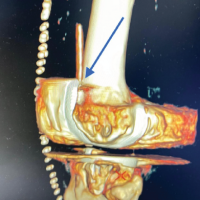

Under general anesthesia with the patient prone, a straight incision was made along the lateral border of the right scapula; the 15 × 6 × 6 cm, lobulated, bony mass was noted which was delivered en bloc (Fig. 4). The tumor was lobulated with a cartilage cap, and continuity between the medullary canal of the lesion and the native scapula confirmed the diagnosis of osteochondroma. Intraoperative clinical picture and fluoroscopy ensured complete resection. Post op X-ray confirmed the same.